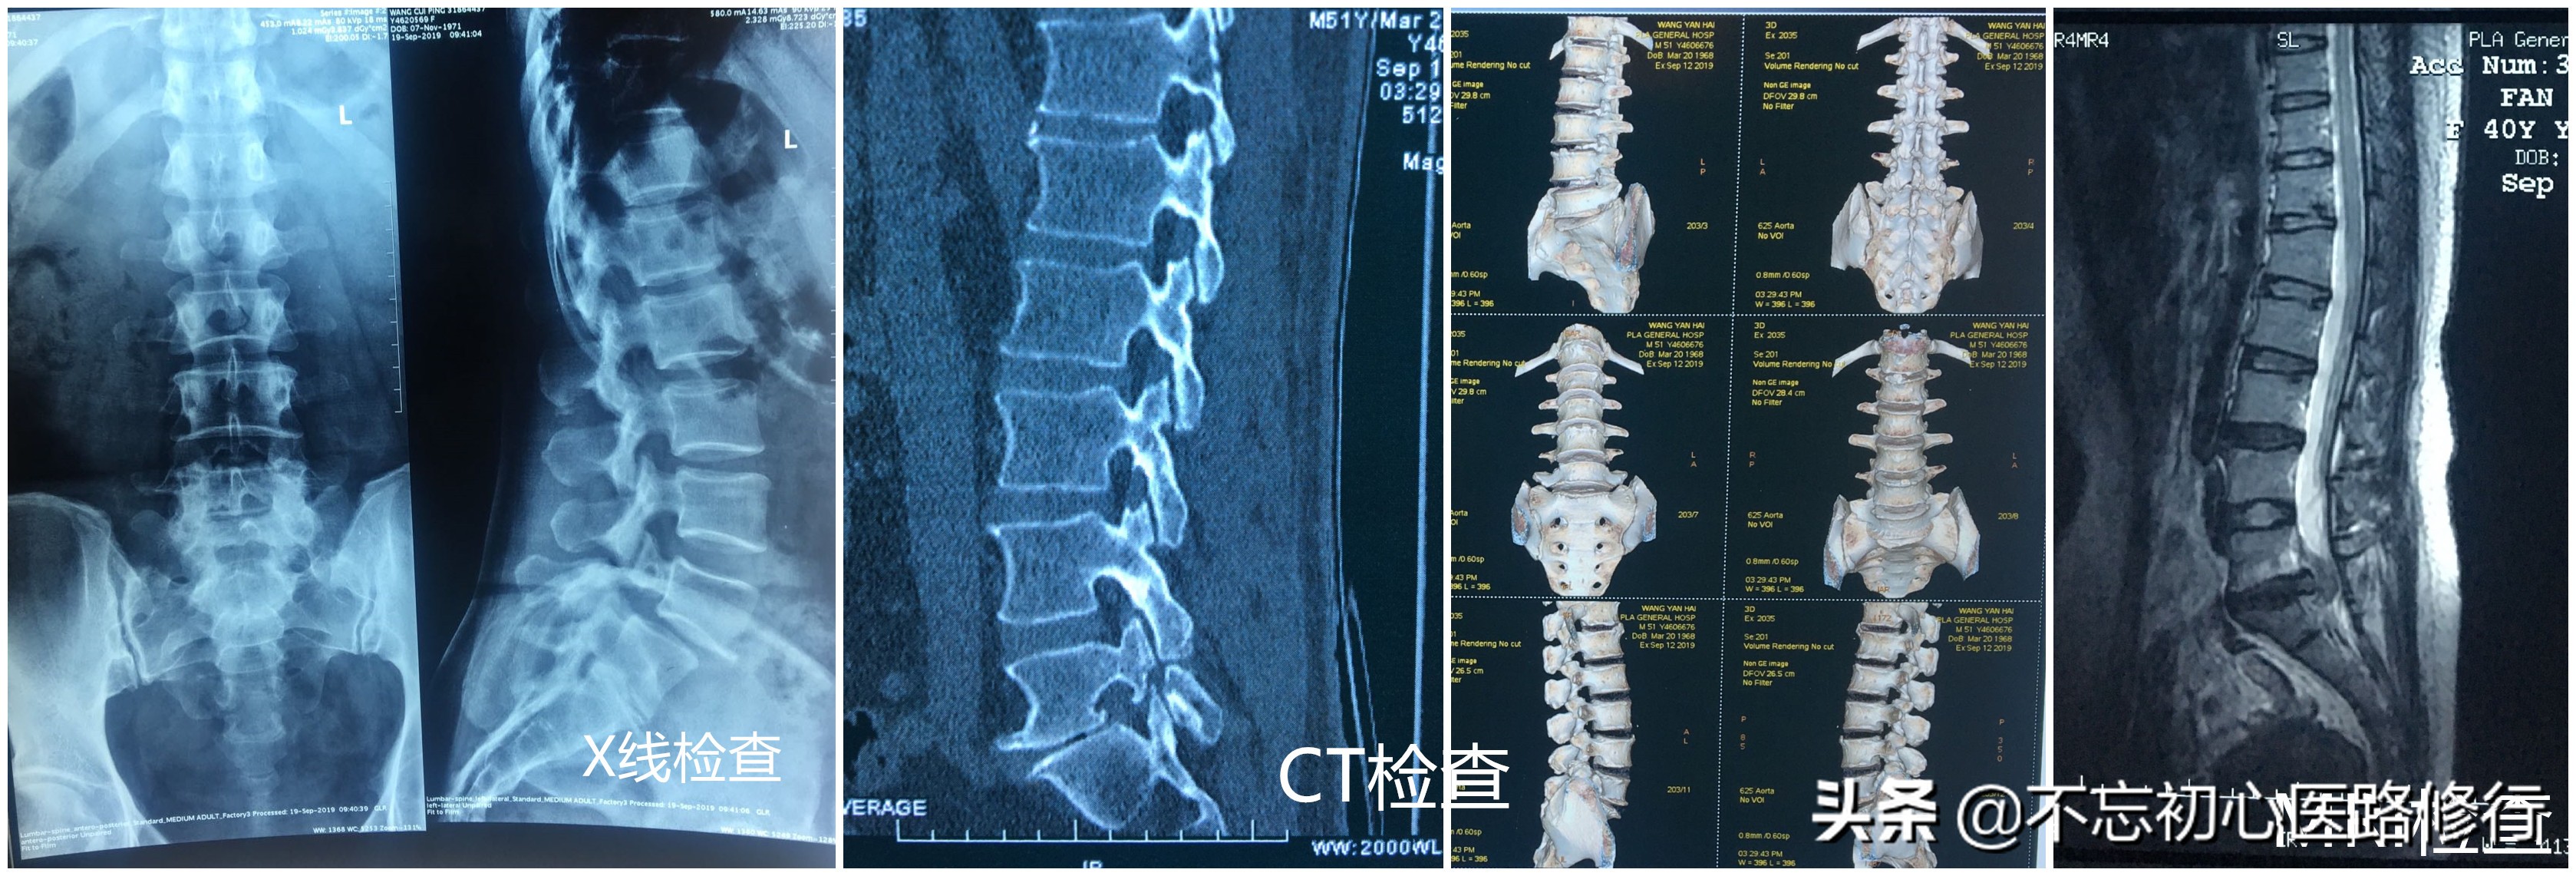

1.X线平片: 是最常规的检查,一般摄正侧位,若怀疑有不稳要摄屈伸动力位及双斜位。腰椎平片可完全正常,很多会出现:腰推侧弯、腰椎间隙宽度狭窄、腰椎生理前凸变小或消失,严重者甚至反常后凸,还可以看到纤维化钙化,骨质增生等。

2.CT检查: 能更好的显示脊椎骨性结构的细节。能清晰地了解到腰椎管的容积,关节突退变、内聚、侧隐窝狭窄以及黄韧带肥厚与后纵韧带骨化等。

3.MRI检查:能清楚的显示出人体解剖结构的图像,可以观察椎间盘的退变情况,髓核突出的位置和程度,有无椎管其他占位性病变等。